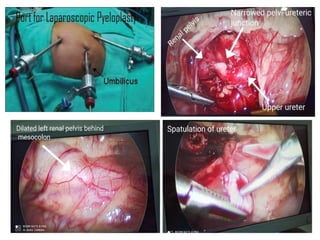

Laparoscopic Surgery:

Transperitoneal approach

Retroperitoneal approach

Dismembered pyeloplasty Modified AndersonHynes Pyeloplasty for PUJ obstruction Excision of redundant pelvis Excision of pathological PUJ segment Spatulated wide ureteropelvic anastomosis Dependent Water tight Tension free anastomosis